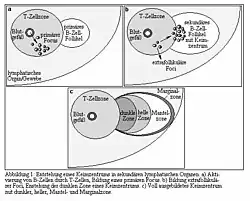

The mantle zone (or just mantle) of a lymphatic nodule (or lymphatic follicle) is an outer ring of small lymphocytes surrounding a germinal center.[1]

It is the location of the lymphoma in mantle cell lymphoma.

Mantle zone expansion may be seen in benign, such as Castleman disease, and malignancy, i.e., Mantle cell lymphoma. Tcl-1 is expressed in the mantle zone.